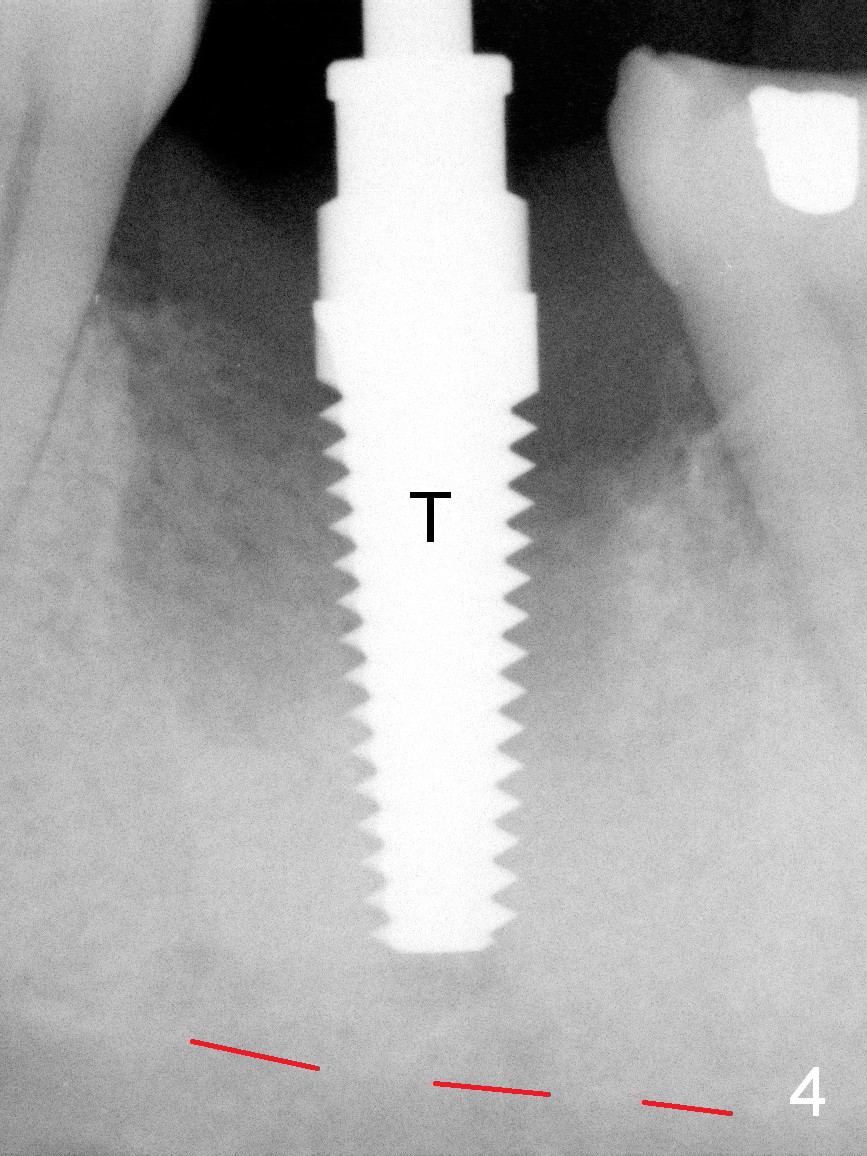

A 37-year-old lady (MP) presents to clinic with chief complaint of bad smell from lower right crown (Fig.1: #19; red dashed line: superior border of the Inferior Alveolar Canal). One of the most prominent pathologies is fracture of the distal root (<). After extraction, the socket is treated with 2% Xylocaine/1:50,000 Epinephrine. The coronal distobuccal plate is defective. Osteotomy is initiated as lingual as possible. The 1st intraop PA shows that the osteotomy is shallow and distal to the almost non-existent septum (Fig.2 S). The osteotomy is intended to move more mesially, but the result is not obvious when 4.5x14 mm drill is in place (Fig.3 D). The depth of the osteotomy is increased by 3 mm; a 5x17 mm tap is stable (Fig.4 T). A 5x12 mm implant (Fig.5 I) is placed until it cannot be turned. The implant is higher than the distal crest (^). In addition there is space apical to the implant (Fig.5*). After 5 mm drill is used, the implant is seated deeper with insertion torque < 35 Ncm (Fig.6). It suggests overprep. Anyway, an immediate provisional is fabricated after placement of an abutment (A). After reline, the provisional fits well. It has to be removed with forceps for occlusal adjustment. Finally the abutment/implant complex turns in the socket with fingers. The rotation/position of the complex is randomly adjusted. When the provisional is cemented, it does not seat completely, but is stable. If the implant osteointegrates, the provisional must play a role in stabilizing the implant. Bone graft is placed in the gap prior to cementation (Fig.6 *).